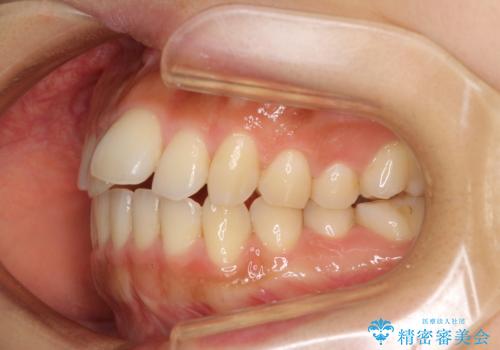

カリエールディスタライザーを併用した、咬み合わせ改善のインビザライン矯正

- 飛び出した前歯と口元の突出感を気にして来院された患者様です。

奥歯の咬み合わせを見ると、上顎が下顎に対して相対的に前方にありました。

口元の突出感を改善するためには、上顎臼歯を後方に移動させた咬み合わせにする必要があります。

インビザライン単体で改善することも可能ですが、達成する可能性が高くないため、カリエールディスタライザーという補助装置を併用して、より確実性を上げることとしました。

奥歯の咬み合わせを改善しながら、並行してインビザラインで歯列を整えることとしました。

カリエールディスタライザーを併用したことで、確実かつ短期間で治療を終えることができました。